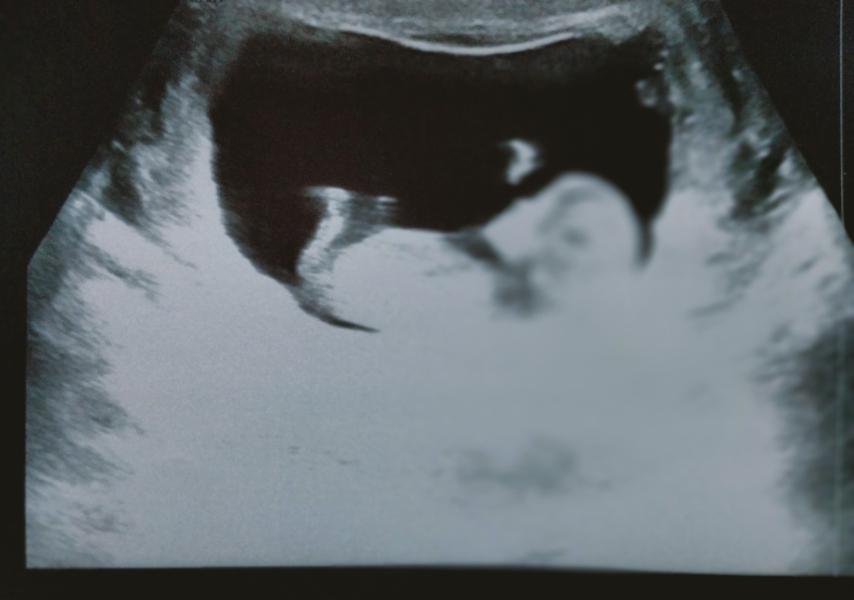

Первое УЗИ: Все хорошо, малыш растет! Как же хочется поскорее родить!

Сделала перво́е узи☺️

У нас все хорошо, малыш растет, помахал маме ручкой 🤗

Так хочется уже поскорее родить 😅